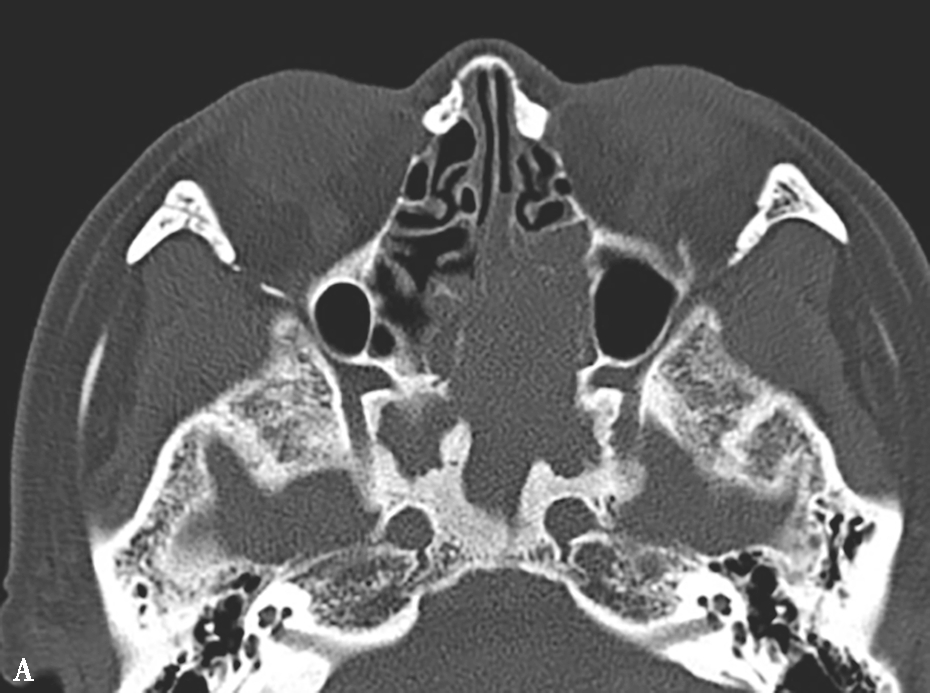

图1-3-23 急性侵袭性真菌性鼻窦炎

A、B.横断面、冠状面CT骨窗,示双侧蝶窦、后组筛窦软组织影,密度不均,窦壁骨质硬化伴局部骨质破坏,累及双侧圆孔、翼管;C~E.MRI横断面T 1 WI、T 2 WI、T 1 WI+FS+C,示双侧蝶窦、后组筛窦内混杂长T 1 、长T 2 信号,窦腔内见斑片状短T 1 、短T 2 信号影,增强扫描边缘强化,前颅底脑膜增厚强化